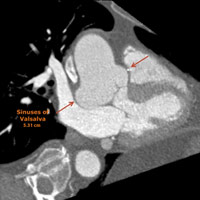

Retrospective, dose-modulated, ECG-gated CT acquisition of the chest was obtained and demonstrated aneurysmal dilatation of the noncoronary cusp of the sinuses of Valsalva (Figure A). The cusp measured 1.5 cm in anteroposterior length and 1.8 cm in craniocaudal length (Figure B). There was associated mass effect on the adjacent left atrium. The sinuses of Valsalva measured 5.3 cm at the widest portion of the aortic root (Figure C). At the level of the main pulmonary artery bifurcation, the ascending and descending thoracic aorta measured 3.7 cm and 2.6 cm, respectively.

• As seen in Table 1, the upper limit of normal for the sinuses of Valsalva ranges from 3.6 to 4 cm. In our case, the patient’s sinuses of Valsalva measured up to 5.3 cm in the axial plane.

| Figure A Valsalva sinus aneurysm (noncoronary cusp) |

Figure B Valsalva sinus aneurysm (noncoronary cusp) 18.2 mm (CC) x 15.8 mm (AP) |

| Figure C Sinuses of Valsalva 5.31 cm |